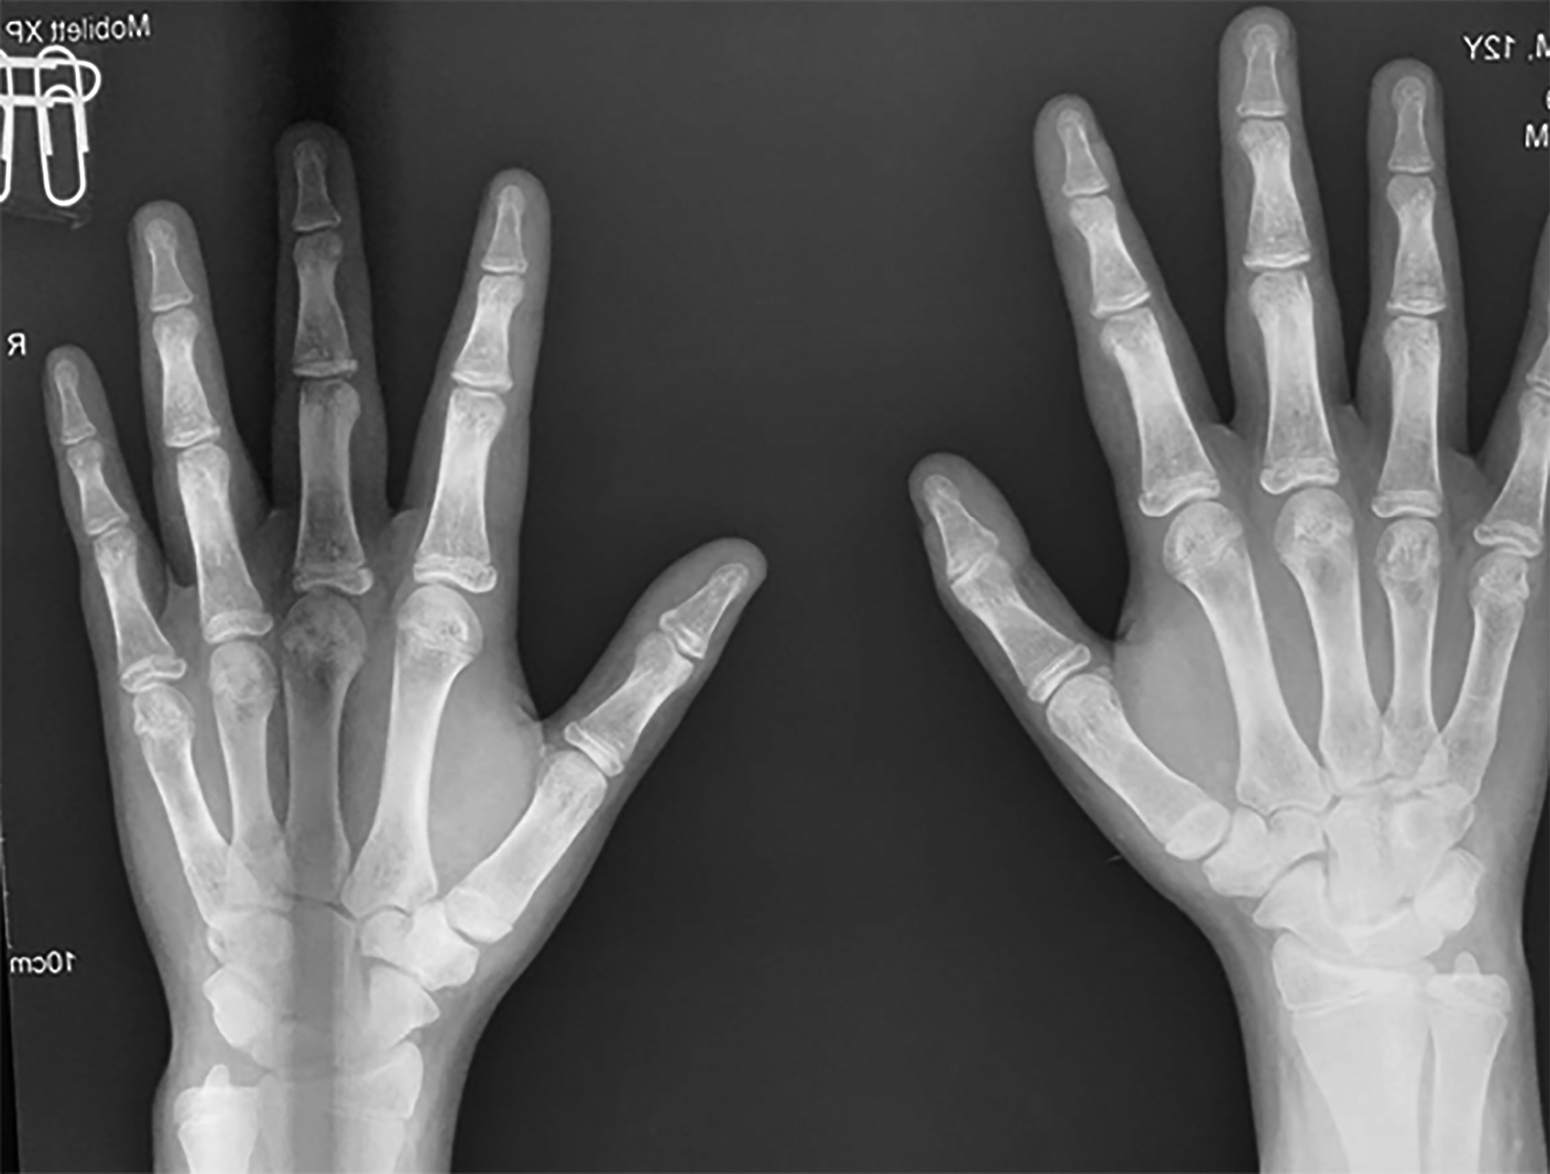

При осмотре в 14,0 лет: рост — 157,5 см (SDS роста=-0,82), рост родителей: мама — 165 см, папа — 175 см, целевой рост — 176,5 см. Получает Л-тироксин 75 мкг в сутки. Половое развитие по Таннеру — 4, объем тестикул — 15 мл. Со слов, первые симптомы полового созревания появились в 9 лет. Костный возраст — 16 лет (рис. 3). В анализе крови на гормоны (табл. 1) все показатели в пределах нормы, кроме уровня инсулиноподобного фактора роста 1 (ИФР-1) — 130 нг/мл (SDS ИФР-1 составил -2,3). Ожидаемый конечный рост без терапии — 162 см.

Рисунок 3. Костный возраст (16 лет) пациента до терапии.